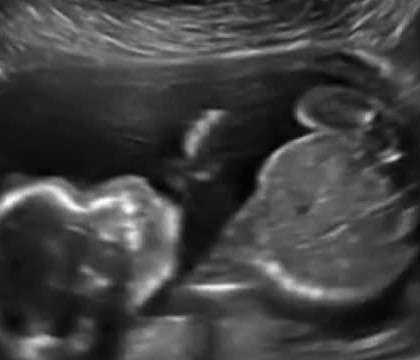

Orice mămică abia așteaptă ecografia de sarcină pentru a-i observa progresele bebelușului. Însă, mare îți este surprinderea atunci când vezi